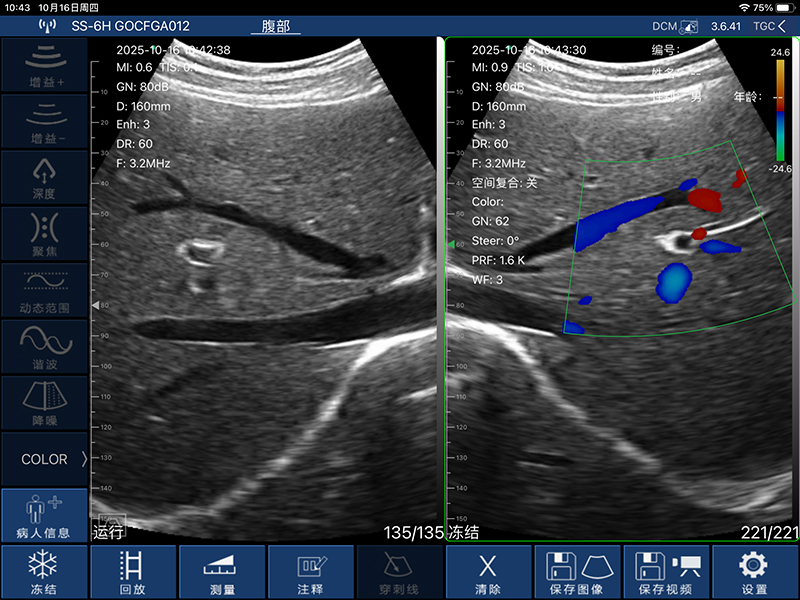

• 显示模式:B、B/M、Color、PW、PDI

• 图像调节:增益、焦点、反相脉冲谐波、降噪

• 穿刺辅助功能:平面内穿刺引导线功能,平面外穿刺引导与血管自动测量功能